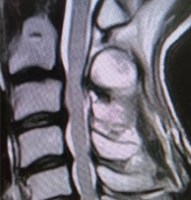

Figure 4: Tumor void filled with allograft, screw scaffold, and bone cement.

Besides it is pleiotropic tumoricidal effect, low viscosity has a working advantage of it increasing in size being inserted and easier to handle as it flows easily and has more working time before it solidifies. Intra-op range was checked, and the construct was found to be stable. Closure was achieved, and post-operative patient was kept in a universal shoulder immobilizer for 6 weeks. Mobilization was started with pendulum exercises, followed by the shoulder range of motion as tolerated by the patient. 1.5-year follow-up imaging reveals no obvious tumor recurrence. Range of motion is of acceptable range and painless.

The treatment modalities for management of GCT’s include chemotherapy, radiotherapy, embolization, cryosurgery, and surgery. Among all treatment methods, surgery remains the only effective treatment for GCT, in most cases. The operative method is determined by the surgical stage of the giant-cell tumor, its size and location, age of the patient, and whether it is a primary tumor or a recurrence [6]. Nonetheless, the ideal form of surgery for this tumor, particularly when arising near joints or when present in weight-bearing bones, remains controversial [7], especially in Campanacci Grade III giant cell tumors, as their massive sizes provide an uphill task in reconstruction and demands case-specific planning from the surgeons. Surgical options include intralesional curettage with bone grafting and/or cement or segmental resection and reconstruction with allograft or prosthesis. The goal of surgery in current times is not only to prevent recurrence by completely removing the tumor but also to maintain adjacent joint function. The evaluation of function, described by Musculoskeletal Tumor Society score (MSTS) adequately gauges the patient’s acceptability of a given procedure [8]. While wide resection and reconstruction minimize tumor recurrence, it fails to provide acceptable functional outcomes, especially in the shoulder joint after treatment of proximal humerus lesions. Intralesional curettage has a higher reported recurrence rate but performs much better on the acceptability scale. Therefore, joint-sparing surgery and careful curettage with the use of adjuvants should be the treatment of choice whenever possible [9]. Grade III osteoclastoma can be treated by intralesional excision, provided the articular surfaces and part of the metaphysis are intact [8]. In younger patients, intra-lesional curettage and reconstruction provide optimum outcomes with minimal chances of recurrence and higher MSTS scores [10]. This has been a major shift in management as high-grade GCT’s were conventionally treated with wide resection due to fear of recurrence [11]. This shift can be attributed to adoption of combined cauterization methods – mechanical (high speed burr), chemical (use of adjuvants like phenol, Hydrogen peroxide, ethanol, and zinc chloride) [12], and thermal (use of bone cement in reconstruction of the cavity) [13], to attenuate the risk of recurrence. Reconstruction using the sandwich technique – in which allograft is placed in the subchondral region and is overlaid with a layer of gelfoam and the rest of the cavity is filled with cement [14] Sandwich technique has been highly popular since first described by Campanacci as it circumvents the disadvantages of both, the bone cement and bone graft when used alone [14,15]. While bone cement helps with immediate stability and early post-operative mobilization, tumoricidal effect via heat generation and easier detection of recurrence as it is easily visualized at the bone-cement interface [16]. It also provides a technical advantage as the plasticity of cement during polymerization allows complete filling of a tumor cavity with irregular confines, and the polymer can be firmly molded around metallic implants [17]. However, it may result in but subchondral articular cartilage damage and joint destruction, and hence, increases the risk of requiring arthroplasty in the long term [13]. The shortcomings are tackled by the layer of subchondral bone graft, as it limits the thermal destruction of the cartilage, as well as provides structural support to the joint. Another advantage that using bone graft provides is a permanent reconstruction of the joint once the graft has completely incorporated into the native bone. The two components of the sandwich technique have a synergistic effect of reducing post-operative complications without increasing the rates of recurrence [18]. However, the vulnerability of this technique of curettage and cementation lies in the high fracture risk, which is caused due to the early loading of the bone and sub-optimal fixation of the cement in the cavity [19]. To alleviate the risk of post-operative fractures, various methods of internal fixation have been tried. These include, in increasing order of stability, Steinmann pins, interdigitating screws [17,20], and locking plates [21]. While inter-digitating screws were relatively less stability as compared to locking plates, they compensated in terms of technical feasibility as they could be inserted directly under vision [17], reduction in operative time, and minimal dissection was required further than what was already done for the curettage, all of which the author believed to be pivotal in the outcome for this patient with a deficient immune system [20]. Toy et al., in a biomechanical study of distal femur defects, furthered the case for this system. They proved that since the screws crossed the midline and had purchase on healthy bone on the opposite side, they allowed the cement mantle to remain stable, thus transferring most of the load to the bone away from the defect and therefore, if a fracture were to occur after this reconstruction, it would most likely be an fracture away from the cavity, which would not only be easier to treat but also would not necessitate any removal of implant. Even though the findings of this study cannot be directly applied to other anatomical sites, the author believes that the principles of augmenting the cementation with screws in a cross-beam construct can be adopted and applied to create a configuration custom to the area of the lesion, as it is the configuration of the screws and not the screws themselves which helps provide the stability. This could help surgeons circumvent the longer incisions and use of excessive hardware while achieving a similar level of stability and ease of future implant removal. The author used an interdigitating cancellous screw in the cavity of the proximal humerus in a pre-determined sequence to cater to the needs of the shoulder joint during its movements, protecting the soft tissue envelope. The screws helped create a scaffold and increase the core strength of the construct. Complimenting this with bone cement and a layer of sub-chondral bone graft to fill the cavity helped us achieve a stable construct in a minimally invasive way.(Fig.5)